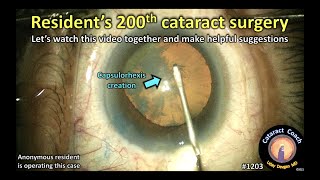

Why you MUST learn Phaco-Chop (Resident Cataract Surgery Case) CataractCoach 1203: resident surgeon's 200th cataract surgery

CataractCoach 1203: resident surgeon's 200th cataract surgery Tough cataract surgery case for a resident!

Why you MUST learn Phaco-Chop (Resident Cataract Surgery Case) CataractCoach 1203: resident surgeon's 200th cataract surgery

CataractCoach 1203: resident surgeon's 200th cataract surgery Tough cataract surgery case for a resident!